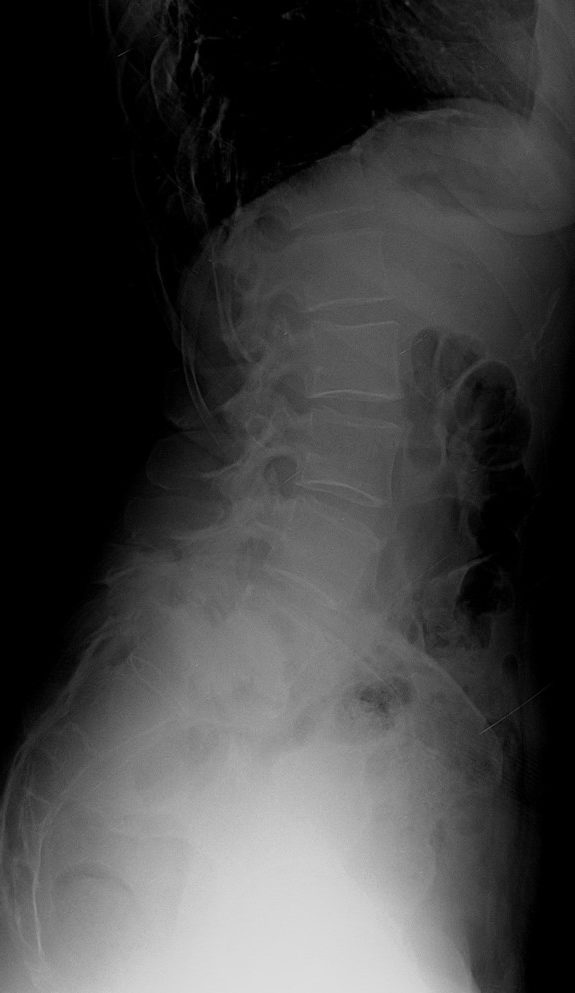

51 Yaşında Kadın Hasta

Bel ve sağ bacak ağrısı

NM normal

Ameliyat Öncesi